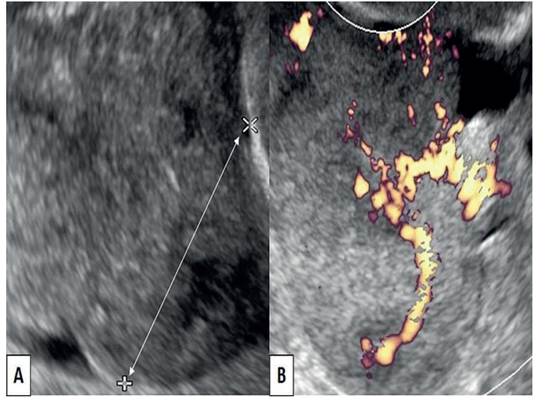

La ecografía pélvica mostró una tumoración heterogénea, principalmente sólida, con bordes irregulares cerca del ovario derecho y en la cara posterolateral derecha del útero, que medía 24 x 22 x 20 milímetros. Fue difícil determinar su origen porque los anexos y el útero presentaban cambios atróficos asociados con la edad. La vejiga también aparecía normal, sin cálculos. La presencia de flujo sanguíneo fue evidente en la ecografía Doppler color (figura 1). No se encontró evidencia de ascitis o metástasis. La resonancia magnética pélvica reveló una lesión sólido-quística redonda bien definida de 3 x 2 x 2 centímetros en el anexo derecho y mínima cantidad de líquido libre en el fondo de saco de Douglas. La radiografía del tórax no mostró alteraciones. Los hallazgos de la citología vaginal eran compatibles con cambios atróficos y negativos para malignidad.

Figura 1 imagen ecográfica de anexo derecho. a) tumor anexial globular y heterogéneo solido-quístico. b) vascularización del tumor anexial derecho.